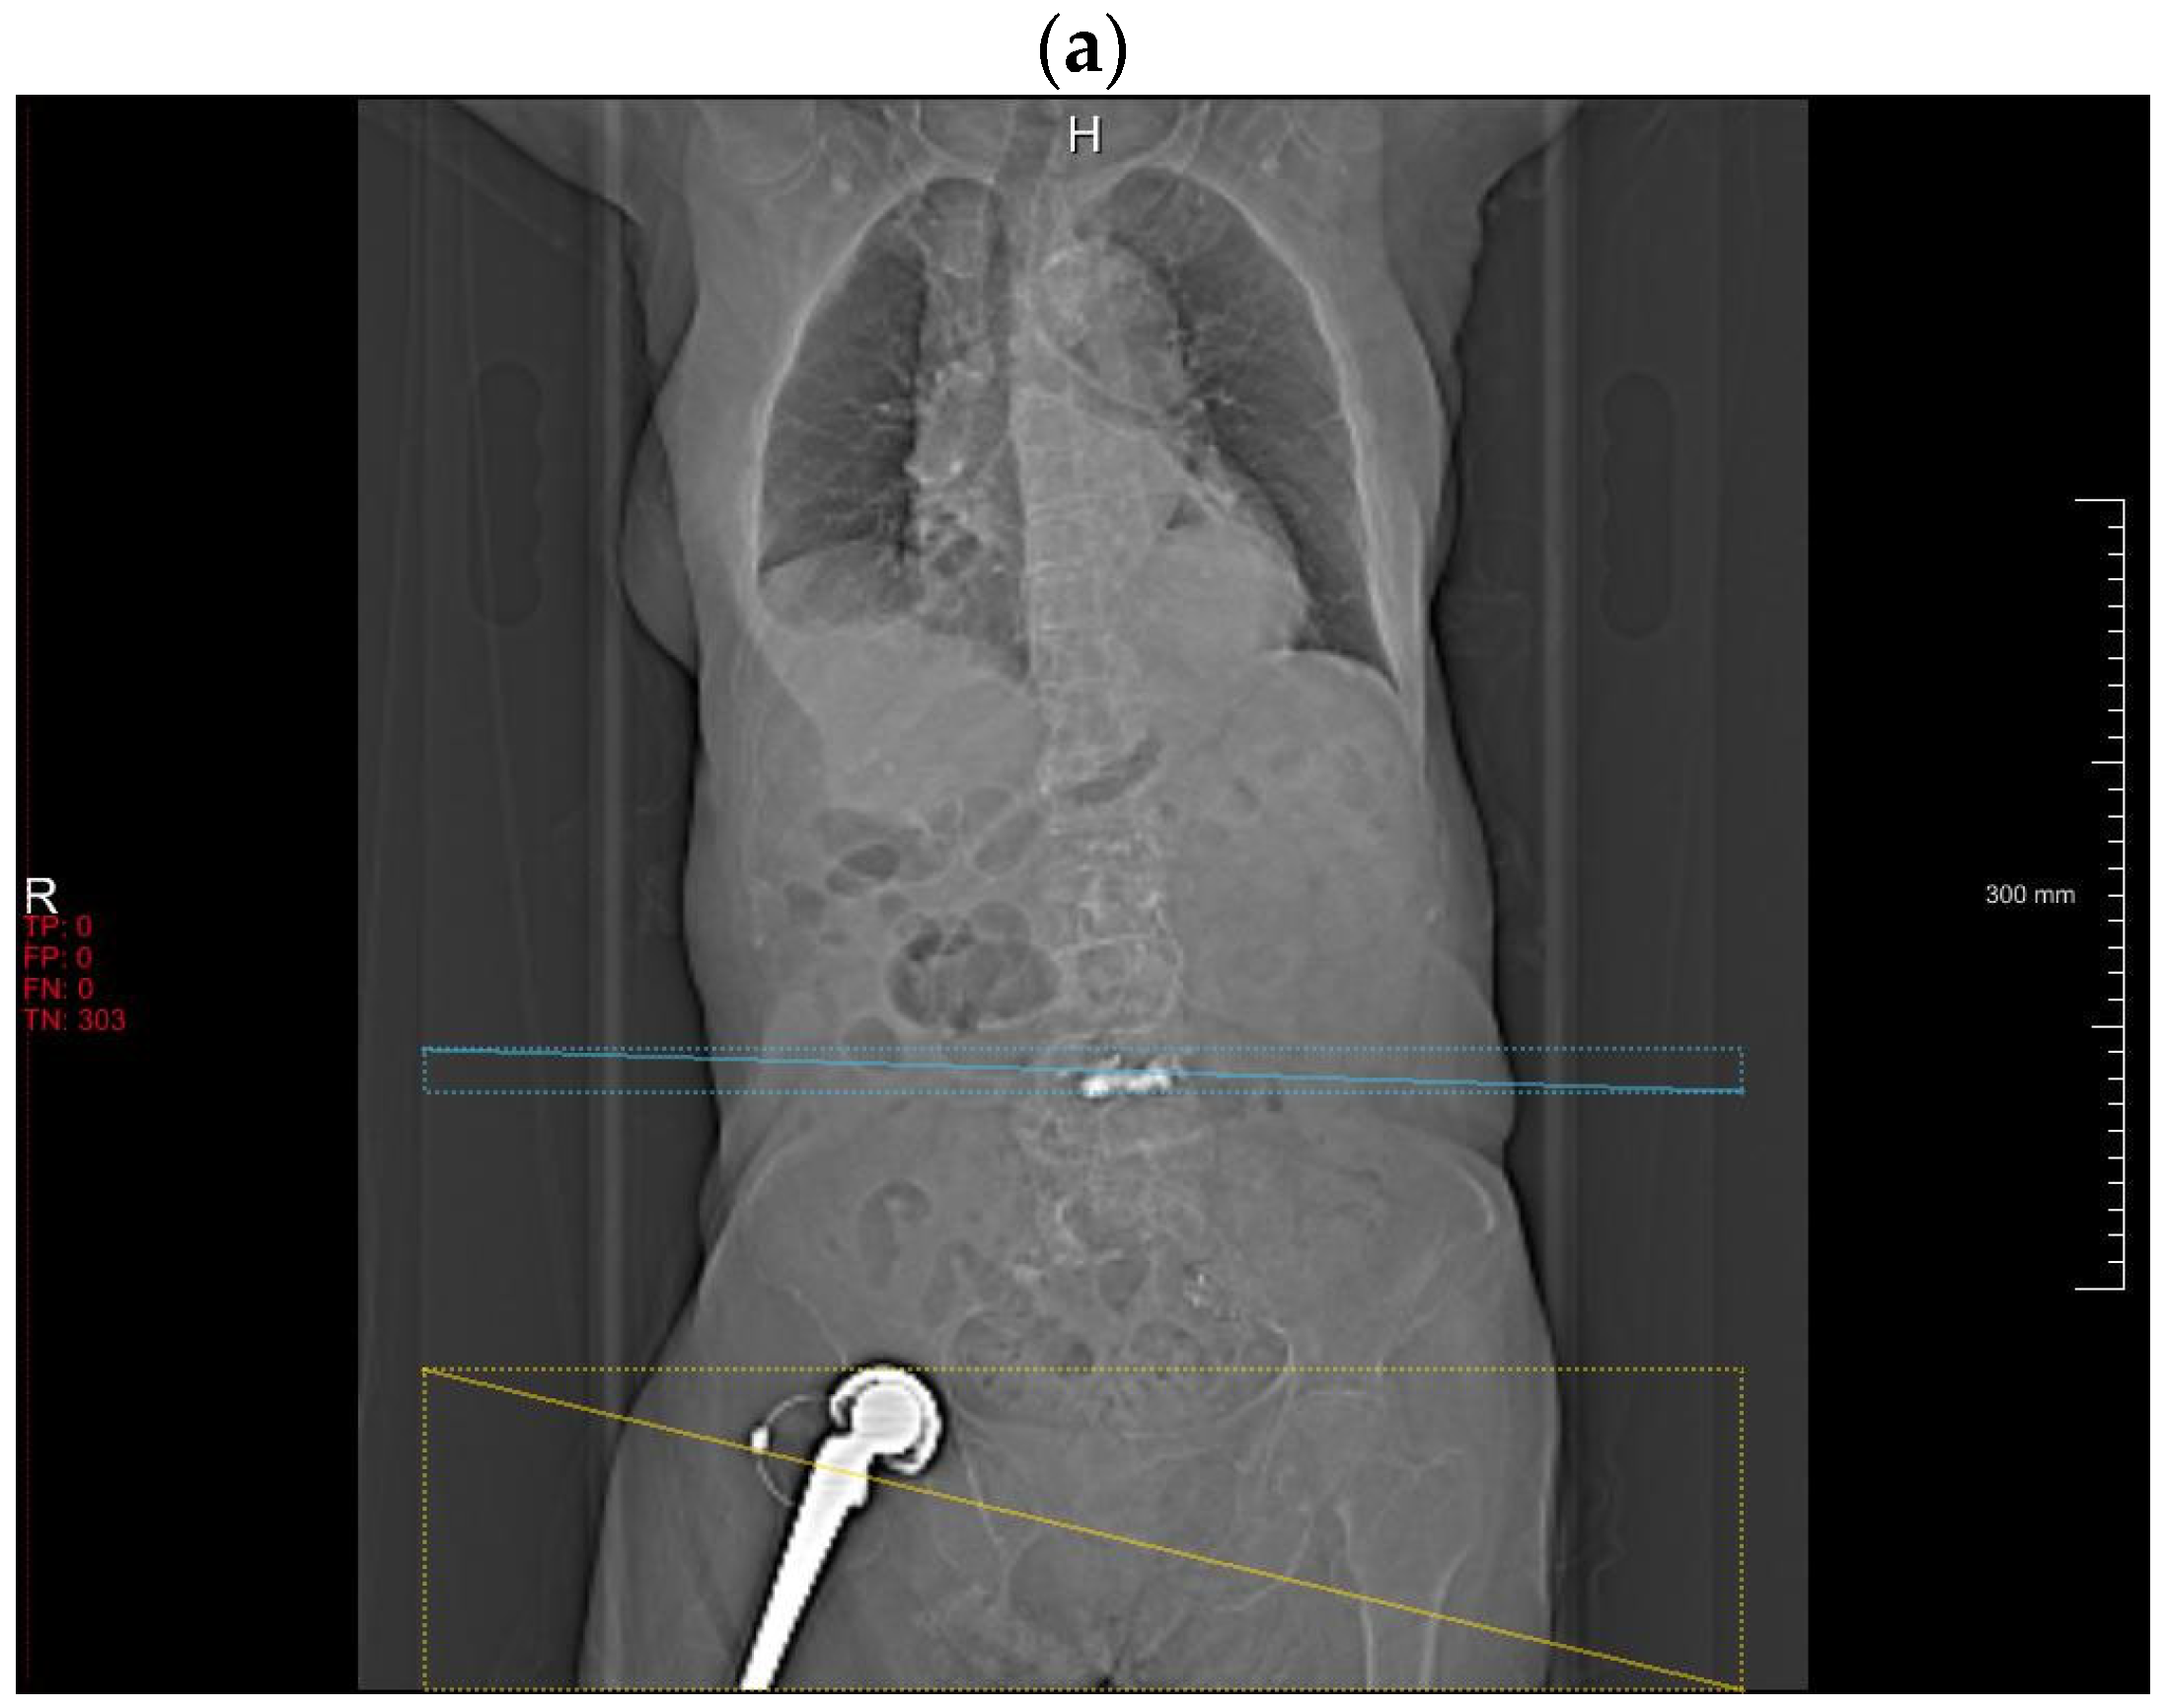

3.2.4. Retrospective Observations for DLA Misclassification

3.2.5. Intersection over Unit between DLA and Radiologists